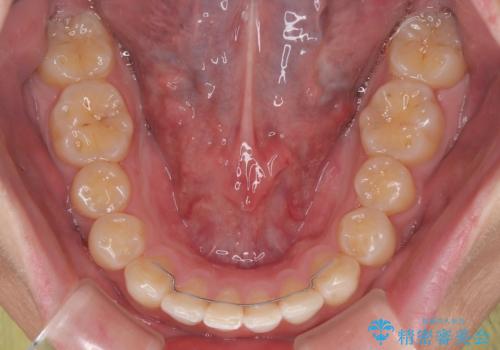

**前歯のデコボコ(叢生)**が整い、歯列全体が美しく改善

シザーズバイトの奥歯も正常なかみ合わせに改善

捻転歯も回転が修正され、全体的に清掃性・咀嚼効率が向上